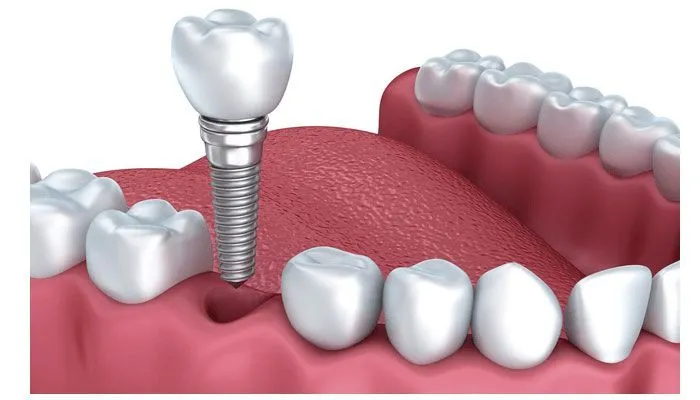

Mất răng không chỉ ảnh hưởng đến thẩm mỹ khuôn mặt mà còn gây ra nhiều vấn đề về chức năng ăn nhai và sức khỏe răng

Mất răng không chỉ ảnh hưởng tới thẩm mỹ mà còn gây ra nhiều vấn đề về chức năng ăn nhai và sức khỏe răng miệng. Trong

Mất răng là vấn đề phổ biến ảnh hưởng không nhỏ đến chức năng ăn nhai cũng như thẩm mỹ khuôn mặt. Để khắc phục tình trạng

Việc mất răng không chỉ ảnh hưởng đến thẩm mỹ khuôn mặt mà còn tác động tiêu cực đến chức năng ăn nhai và sức khỏe răng

Cấy trụ răng là một trong những kỹ thuật nha khoa hiện đại giúp phục hồi răng đã mất một cách hiệu quả, đảm bảo cả về